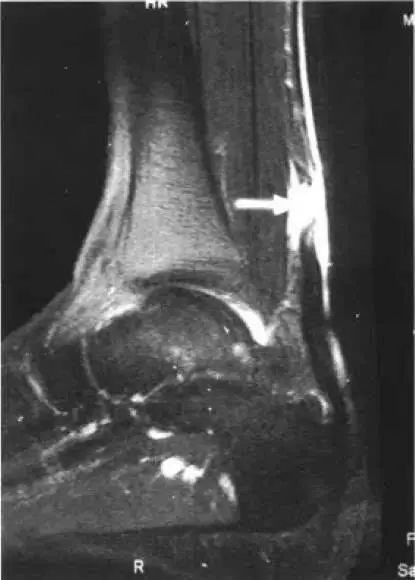

运动医学分析运动损伤案例,运动医学跟腱撕裂

正后方看,可以看到粗黑长的跟腱再中间变得不连续了

白色箭头是跟腱 三角是断裂处

白色箭头是跟腱的断裂部位